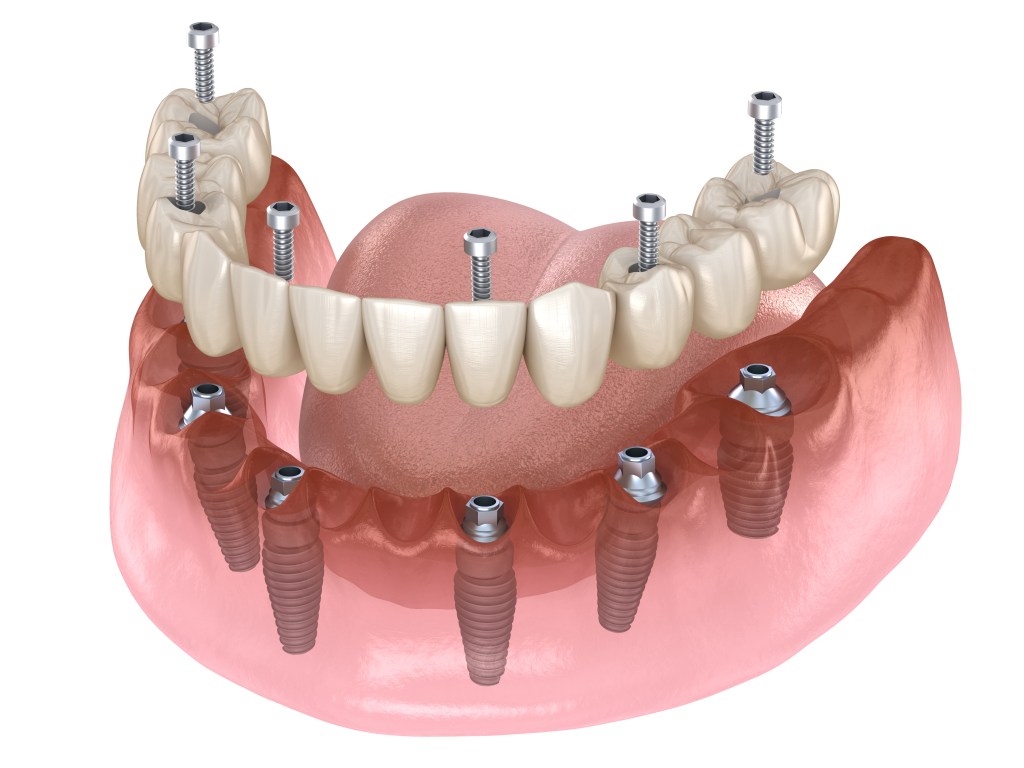

Remplacer l’ensemble des dents manquantes sur toute une arcade par un bridge fixe sur 4/6 ou 8 implants (en fonction de l’anatomie).

Cela représente le traitement idéal lorsqu’il n’y a plus de dents, ou qu’il reste quelques dents qui ne seront pas conservables. Après analyse clinique et radiologique, le Dr Génique pourra vous proposer la solution la plus adéquate pour restaurer la mastication et le sourire.

Après une analyse esthétique, fonctionnelle et radiologique complète, nous avons pu réaliser les extractions des dents non conservables, la mise en place des implants ainsi que la réalisation d’un bridge provisoire immédiat. Des guides chirurgicaux ont été utilisés afin d’augmenter la précision de l’acte chirurgical. 3 mois après, un bridge complet en céramique Zircone a été réalisé

Ici, cette patiente présentait une absence totale de dents du haut compensé par un appareil dentaire complet. Après une planification rigoureuse impliquant des radiographies 3D, scanner, photographies, nous avons pu prévoir sur une matinée la pose de 6 implants à travers un guide chirurgical, ainsi que la mise en place d’un bridge provisoire complet. La patiente est donc repartie avec des dents fixes. 3 mois après, le bridge définitif a pu être réalisée en céramique polycristalline (Zircone)